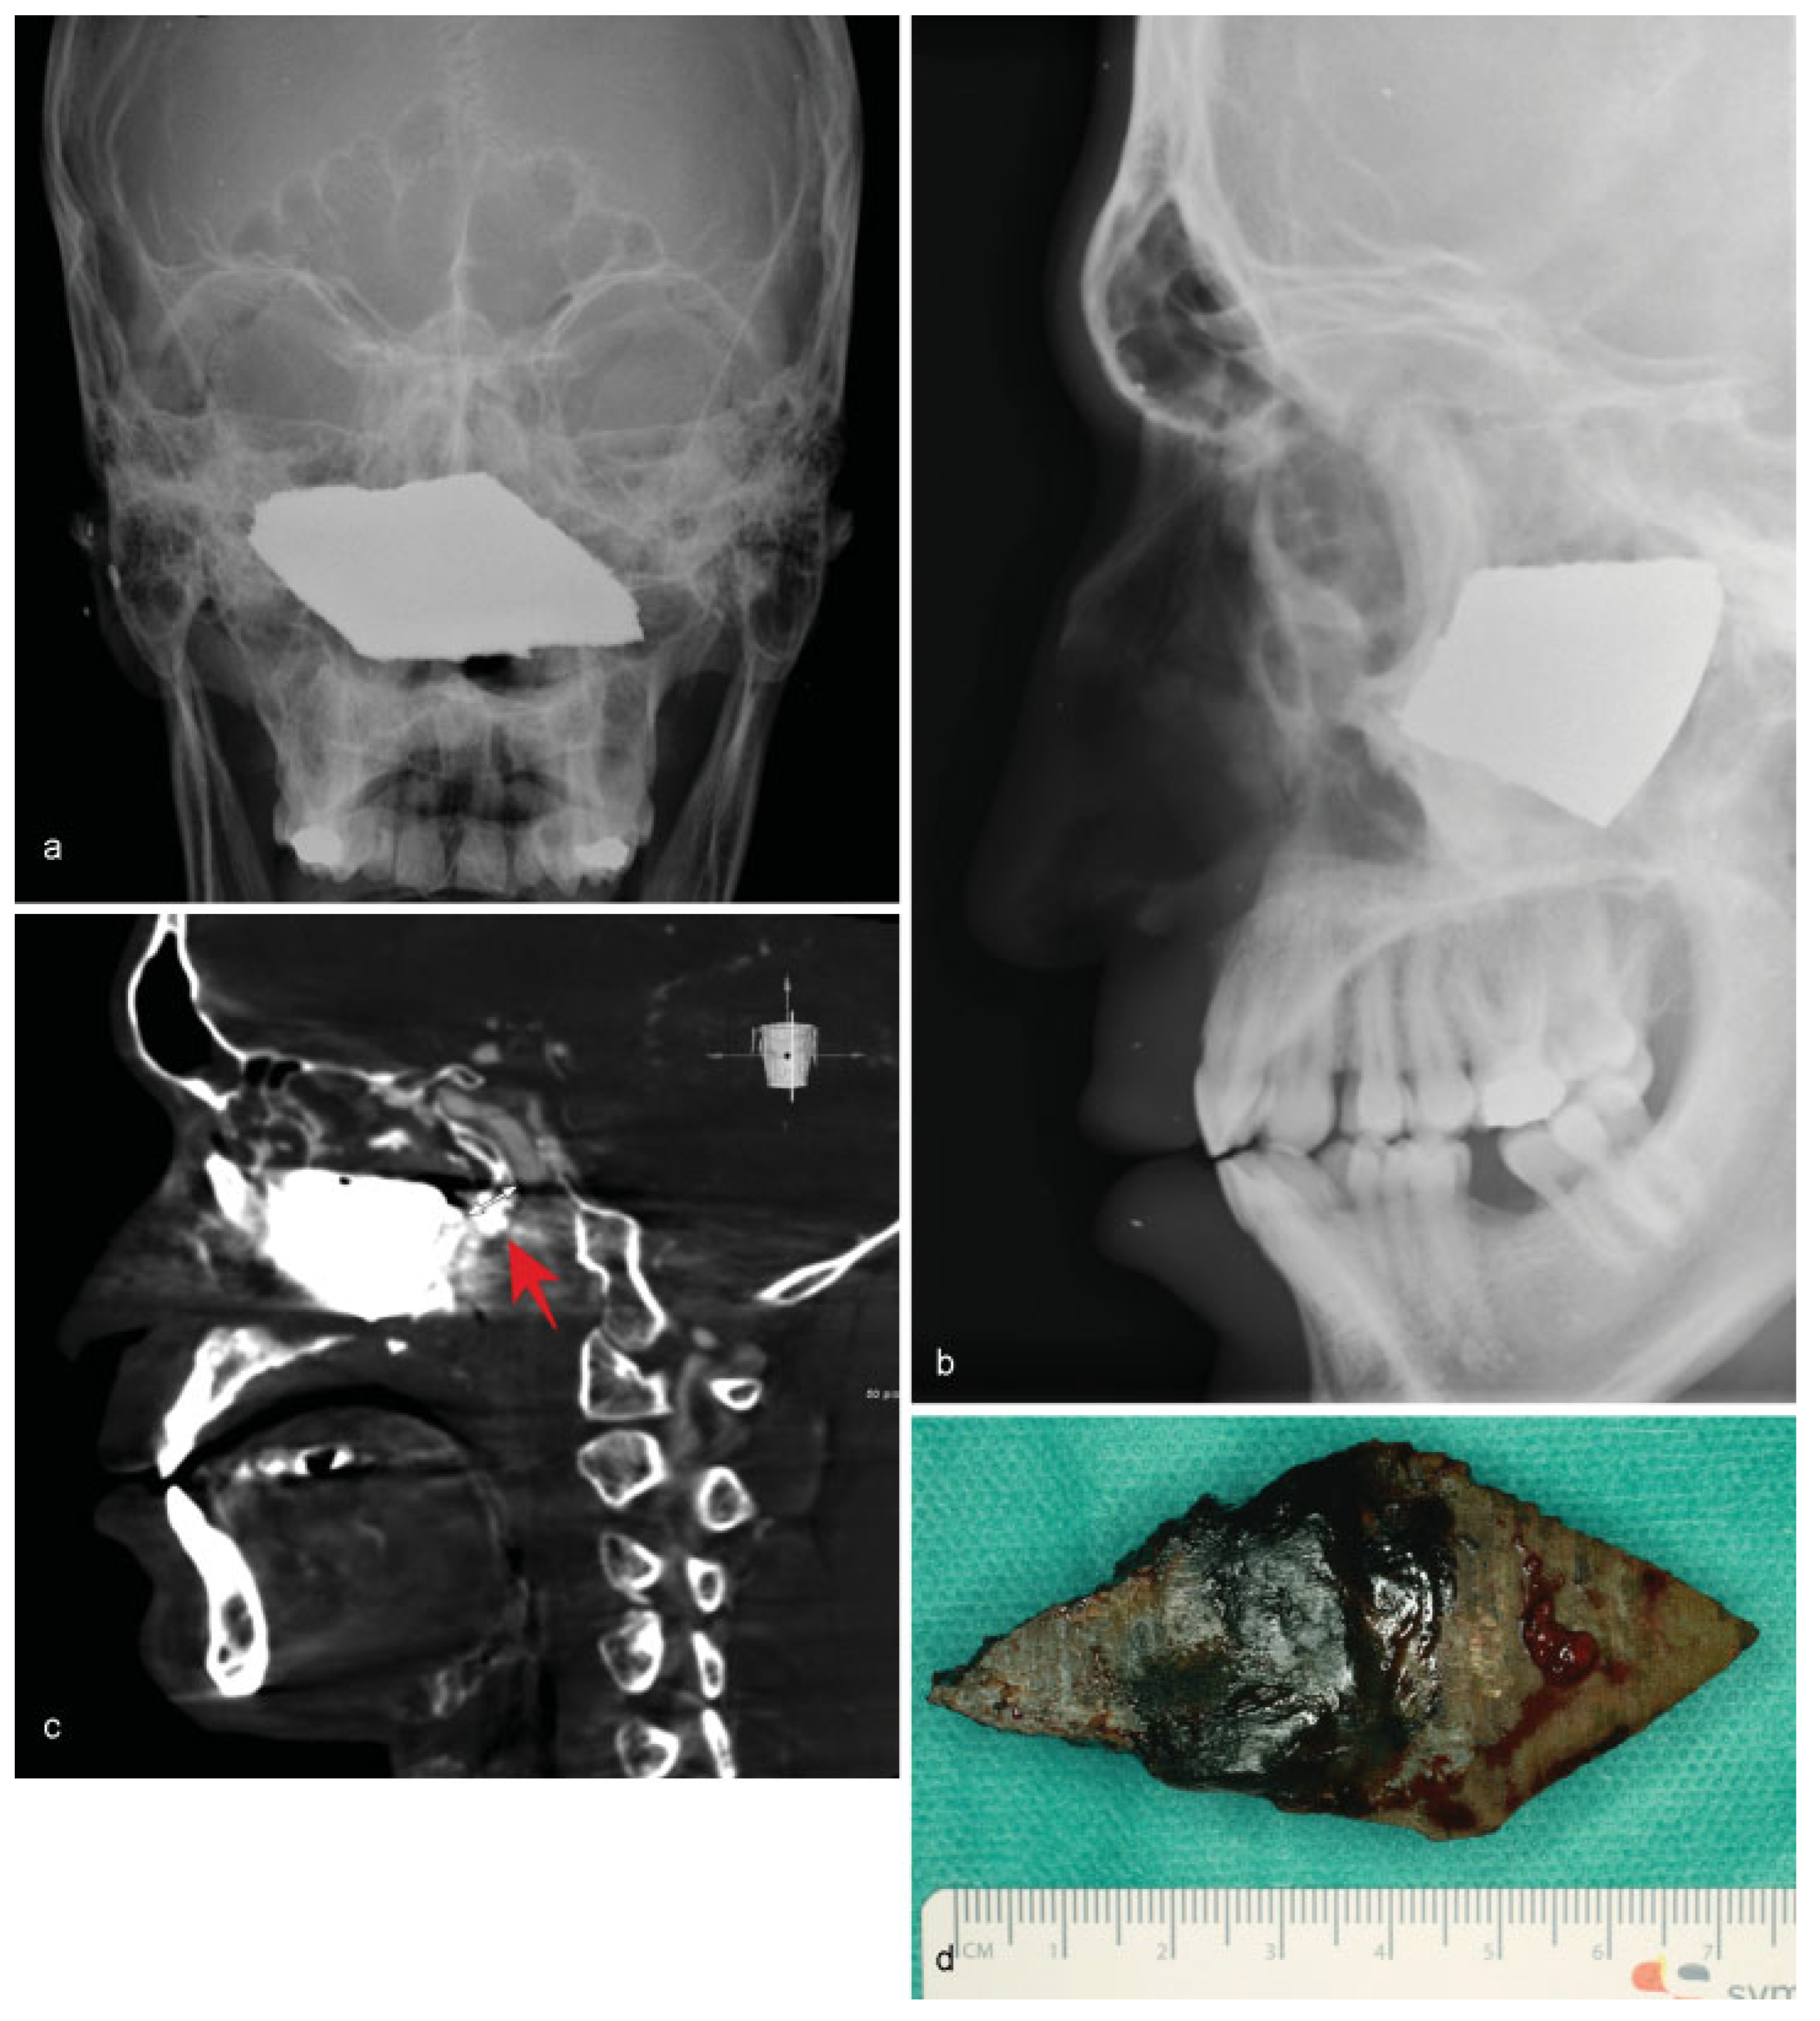

• Case 2: A 4-year-old girl was admitted to the emergency department after tripping while holding a key in her hands, ramming the foreign object into her cheek. Radiological examination confirmed perforation of the left maxillary sinus (Figure 2a). Surgical removal of the key was performed under general anesthesia (Figure 2b). The anterior wall of the maxillary sinus was flipped back without the need for osteosynthetic stabilization due to the young age of the patient. Wound healing showed no sequela.

Figure 2. (a) Lateral skull radiograph showing the radiopaque object penetrating the maxillary sinus. (b) Postoperative image of the removed key.